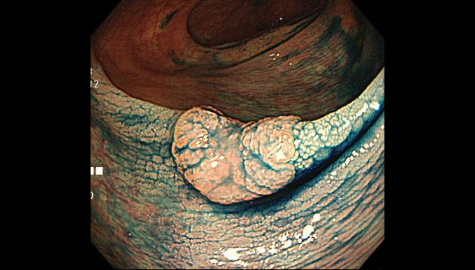

内視鏡で切除可能な早期大腸がんの内視鏡画像です。大腸がんへと進展していても、早期に発見できれば外科的手術ではなく、内視鏡的粘膜切除術にて切除することが可能ですので、早期発見・早期治療がより大切になります。

内視鏡的粘膜切除術にて切除するために、生理食塩水を粘膜下層に注入して、より安全に確実に切除することが可能となります。

高周波スネアと呼ばれるワイヤーを投げなわのようにポリープの根元にかけ、焼き切り切除します。

ポリープ切除後の創部です。完全に取り切れているかを確認します。

クリップにて縫縮することにより、治療後の出血や穿孔などを防止します。クリップは数日から数週間後に自然に脱落し、排便とともに排出されます。

大腸内視鏡検査を初めて受けた方で、早期大腸がんが見つかりました。わずか6分で内視鏡治療は終了しました。

この段階のがんでは、あまり症状は現れません。大腸がんを予防するために、まずは一度内視鏡検査を受けてみることが大事になります。